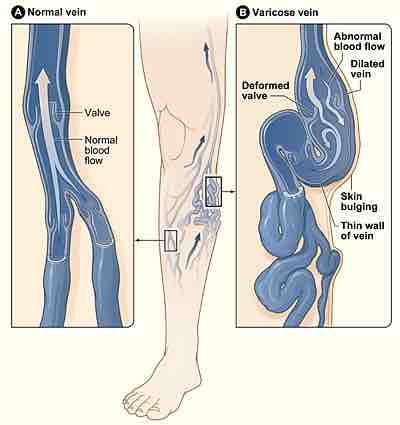

Figure A shows a normal vein with a working valve and normal blood flow. Figure B shows a varicose vein with a deformed valve, abnormal blood flow, and thin, stretched walls. The middle image shows where varicose veins might appear in a leg.

Veins have leaflet valves to prevent blood from flowing backwards; this backflow is called retrograde or reflux flow. The muscles of the leg pump the veins to return blood to the heart against the effects of gravity. When veins become varicose, the leaflets of the valves no longer meet properly, and the valves no longer work. This change is called valvular incompetence, and it allows blood to flow backwards. To accommodate the retrograde or reflux flow, the veins enlarge even more.